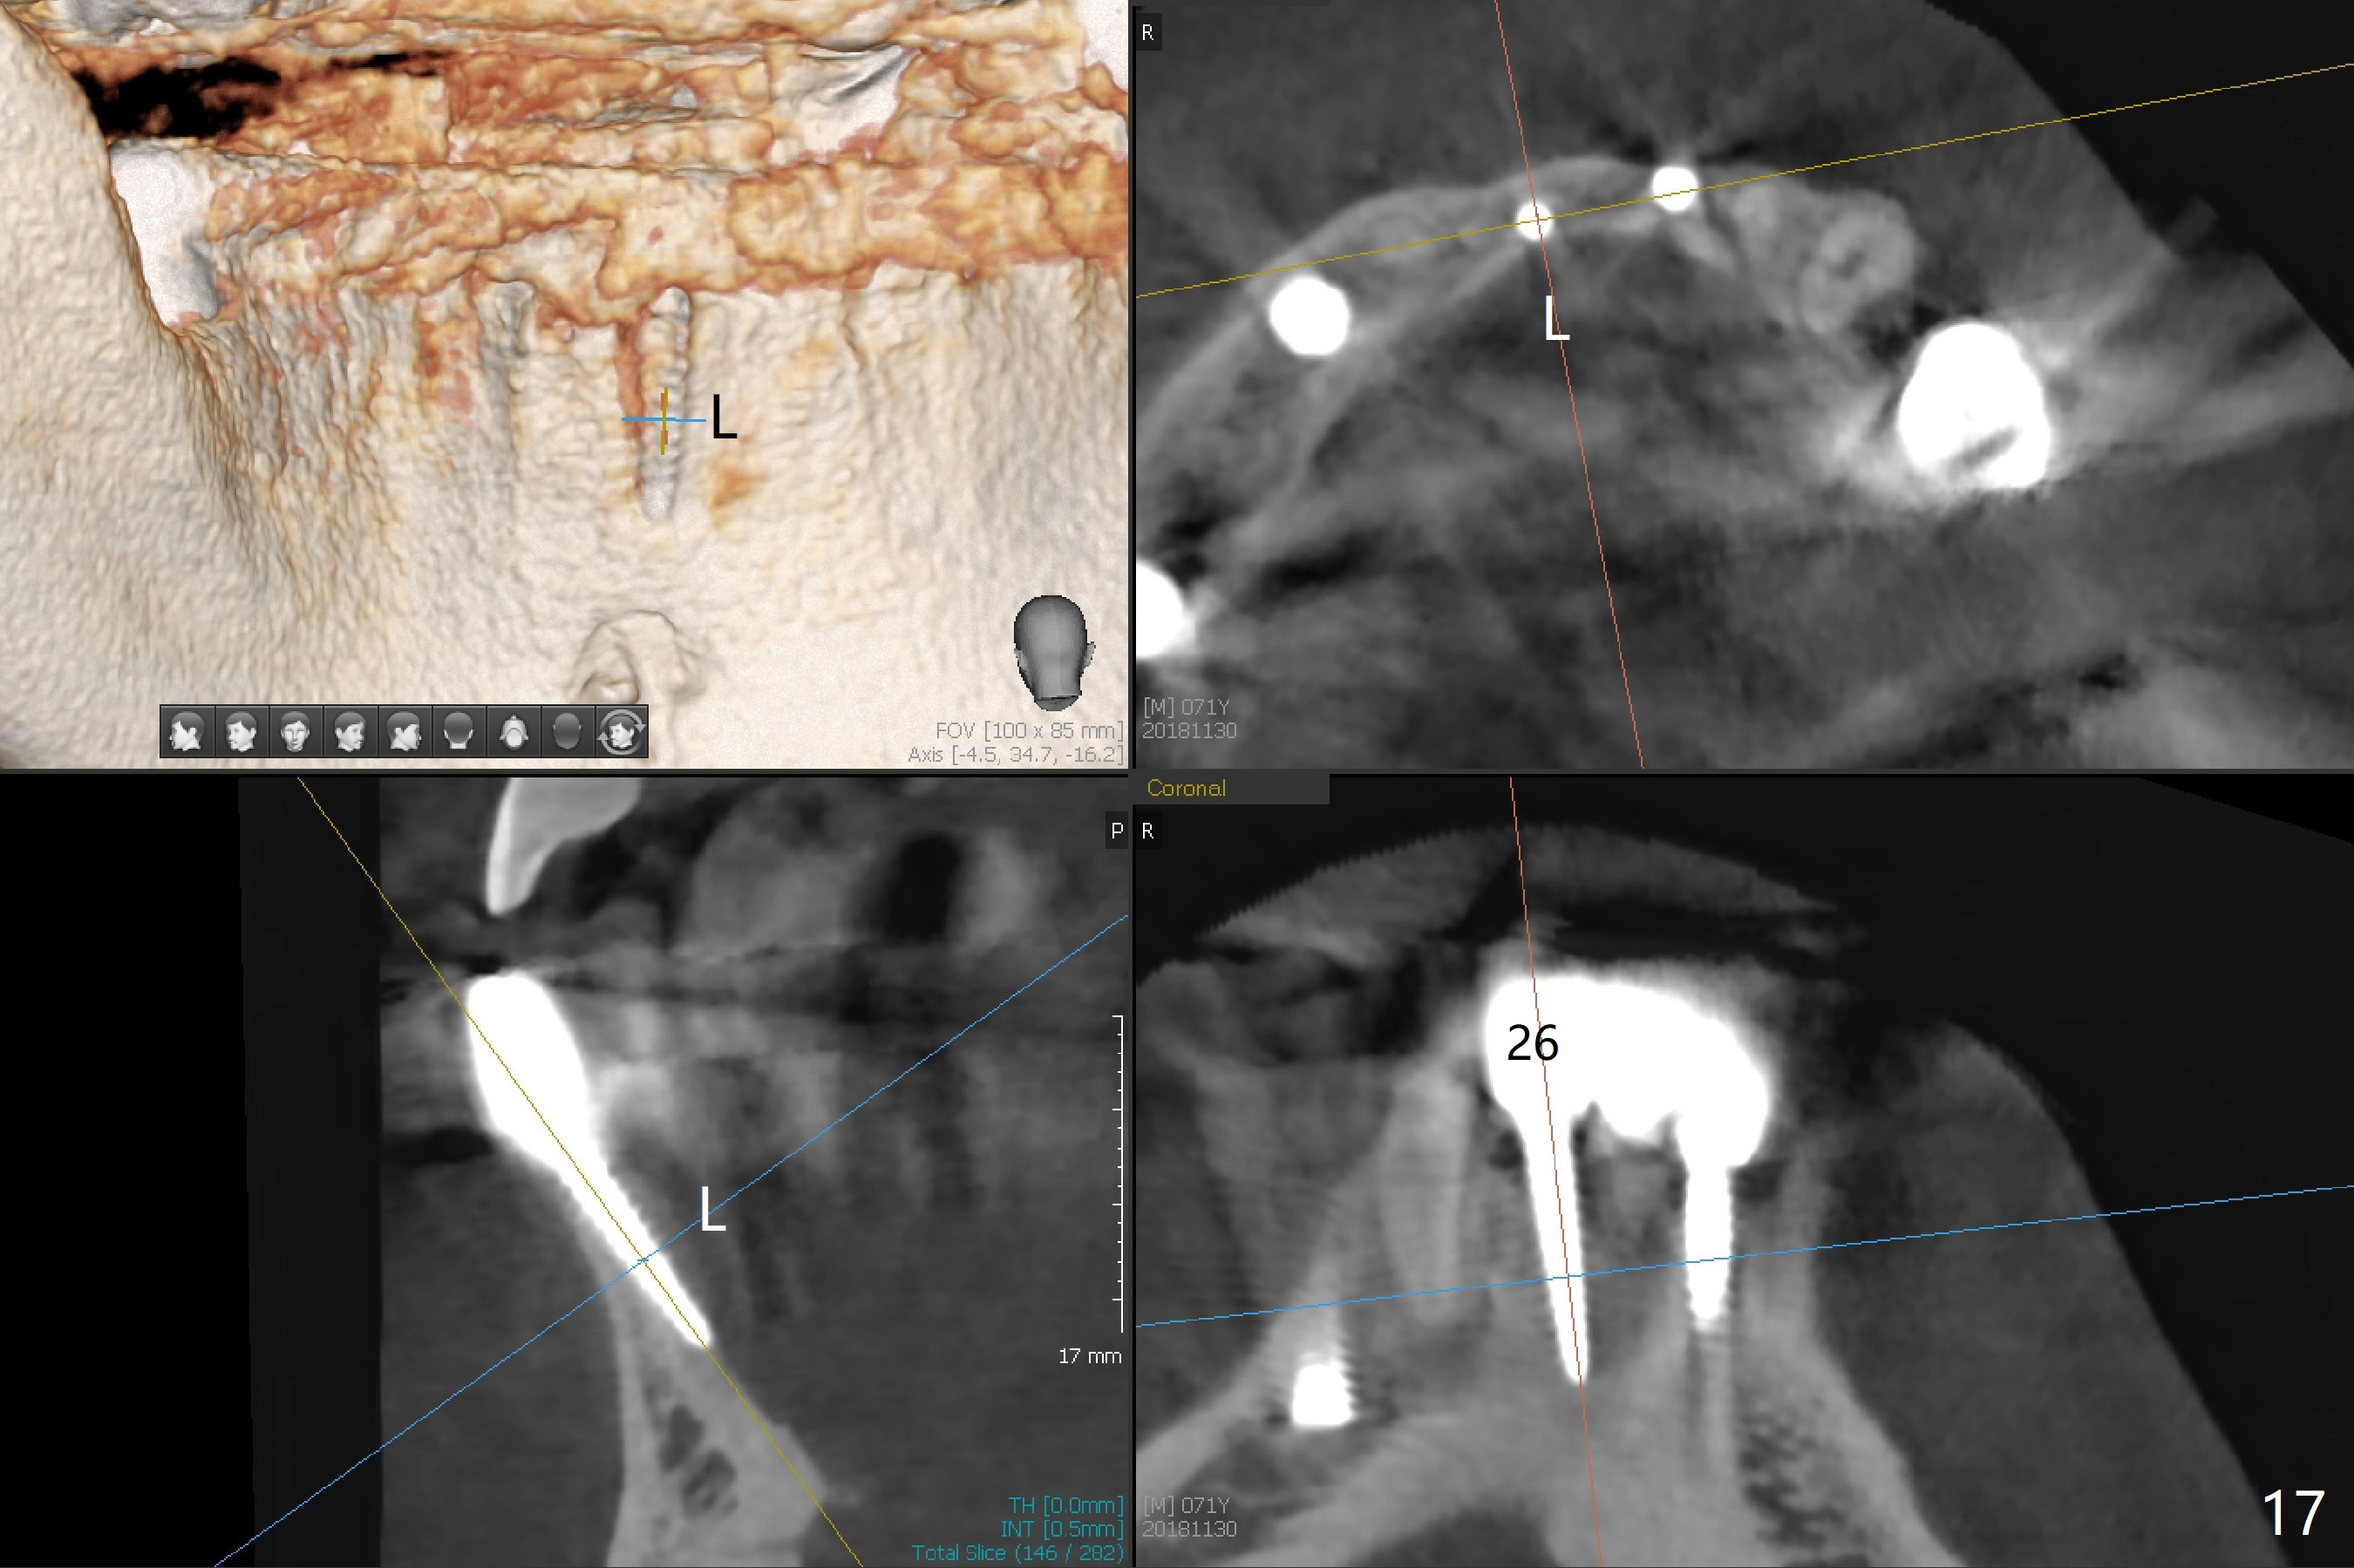

The infection persists at #26 four years 8 months post cementation (Fig.16 *). CBCT is taken. In fact the implant at #26 was placed lingual (Fig.17), while that at #24 buccal (Fig.20). The 2nd option is to remove the implant at #26 and place a 2 mm one at #25 (Fig.18,19). Fabricate a 3-unit cantilever FPD. Take 5x5 cm CT with 1.2 mm drill in place for 10 mm. Change the trajectory and position if necessary.